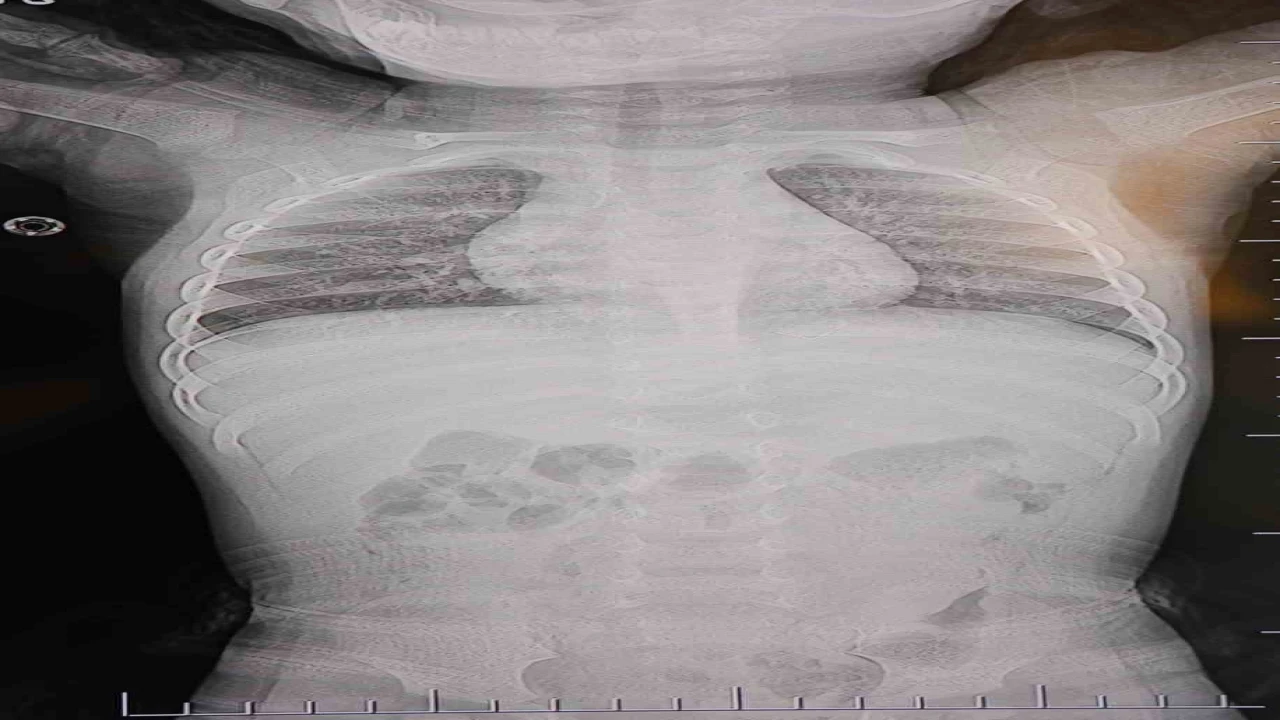

Baba Poyraz, bir gün acil serviste yapılan kontrollerde bebeğin belinde yabancı cisim olduğunu, çekilen filmlerde ise "L" şeklinde zımba teli tespit edildiğini söyledi. Çeşitli hastanelere yönlendirildiklerini anlatan baba, uzun süre müdahale edilmediğini, daha sonra özel bir hastanede yapılan operasyonla zımba telinin çıkarıldığını kaydetti.

"Filmlere baktılar ’L şeklinde zımba teli var, alınması lazım’ dediler"

Poyraz, bebeğin doğduktan sonra sarılık diyerek kuvöze alındığını belirterek, "Bir hafta orada yattı. Sonra çıkardılar, eve getirdik. Eve geldikten sonra gece gündüz ağlaması hiç durmadı. Tekrar hastaneye götürdüm. Kaşınıyordu, bir hafta banyo yaptıramadık. Sonra duş aldırdım, bağırması daha da arttı. Belini açtık, sırtına baktık, bir şey var mı diye kontrol ettik, görünürde yoktu. Hastaneye götürdük, şurup verdiler. Aylar geçti. Daha sonra acilde bir doktor çocuğumun belinde yabancı cisim olduğunu söyledi. 184’ü aradım, şikayette bulundum. Başhekim yardımcısının yönlendirmesiyle tomografi çekildi. O zaman belinde zımba teli olduğu netleşti. Başka bir hastaneye götürdük, ’riskli, 8 yaşına kadar alınamaz’ dediler, geri gönderdiler. Eve geldikten üç gün sonra oğlum bayıldı. Kardeşimle özel hastaneye götürdük. Orada filmlere baktılar, ’akciğere doğru gidiyor, L şeklinde zımba teli var, alınması lazım’ dediler" dedi.